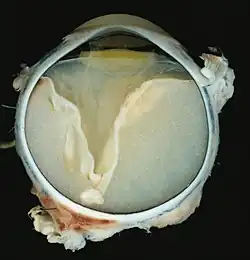

V-förmige Ablösung der Netzhaut durch das Exsudat. -

Vollständige Ablösung der Netzhaut durch das Exsudat.

Eine ausgeprägte Netzhautablösung und ein gelbliches Exsudat unter der Netzhaut, das Cholesterinkristalle enthält, sind charakteristisch für den pathologischen Befund.